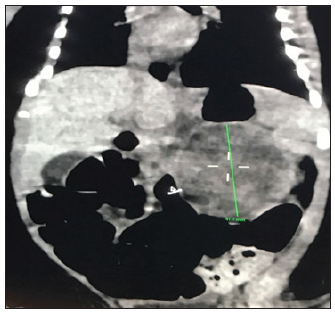

40-year old woman (gravida 4, part 3, abort 1) presented at 34 weeks of gestation for her first pediatric surgery routine antenatal care visit. She had history of preeclampsia; a pelvic ultrasound was performed owing of her prenatal history a cystic mass measuring 4.6X3.6X3.4 cm was incidentally found adjacent to the upper pole of the left fetal kidney (Figure 1). Ultrasound control was performed and revealed the mass to be larger and more solid appearing. Finally, an ultrasound examination at 39 weeks of gestation revealed oligohydramnios and inability to evaluate the left fetal kidneys. Subsequently, the mother underwent an abdominal cesarean delivery of a healthy boy of 3.4kg. APGAR score was 9 and 10 at 1 and 5 minutes, respectively. Physical examination was normal other than a large mass was palpable on upper pole of the left kidney. Postnatal ultrasound examination showed a predominantly solid suprarenal mass deforming the upper pole of the left kidney. The scan demonstrated alteration of kidney structure and displacement of the spleen and intestinal structures (Figure 2). Serum electrolytes, complete blood count, ferritin, and transaminase and catecholamines were normal. Urinalysis and sensitivities of tumor marker levels were normal. Therefore, the patient was admitted to an abdominal exploration with the most probable diagnosis at this stage of a cystic neuroblastoma or an adrenal hematoma as main differential diagnosis.

Figure 2: TC reveal complex solid cystic.